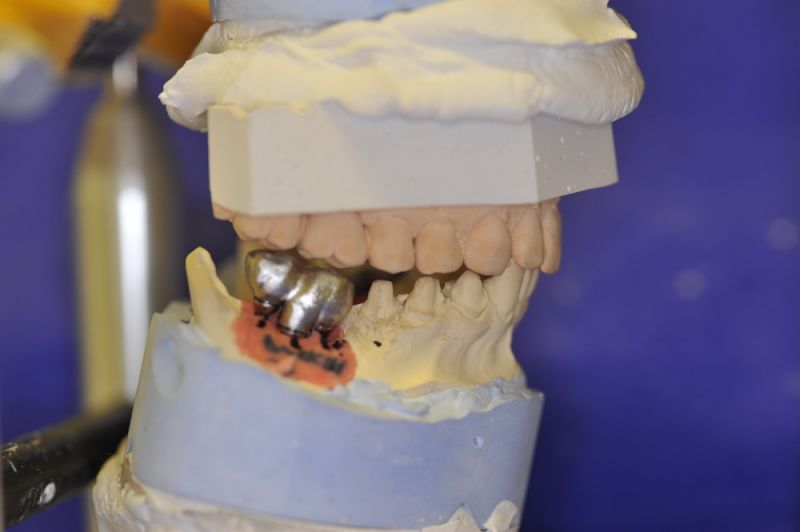

Neuromuskulär zentrierte Bisslage. Gerüste werden unbelastet durch das "Zahnfleisch" nach oben gehoben

Heute war nun Gerüsteinprobe, mit all den Problemen der Umsetzung zwischen Laborsituation und Mundsituation. Siehe Stichpunkt "Schnittstellenproblematik"! was bei Zähnen, auf Grund deren Eigenbeweglichkeit im Kieferkochen kein Problem wäre, ist bei drei unbeweglichen Implantaten ein Riesenproblem. Darüber spricht nur in aller Regel Niemand! Es musste viel fein nachgearbeitet werden.

4 Stunden haben wir heute Temporäre Aufbauten und provisorische Kronen entfernt. Definitive Aufbauten im Munde eingeschraubt. Eine erneute Bissregistrierung durchgeführt und die Arbeit neu artikuliert. Neue Provisorien mussten auch wieder hergestellt werden.